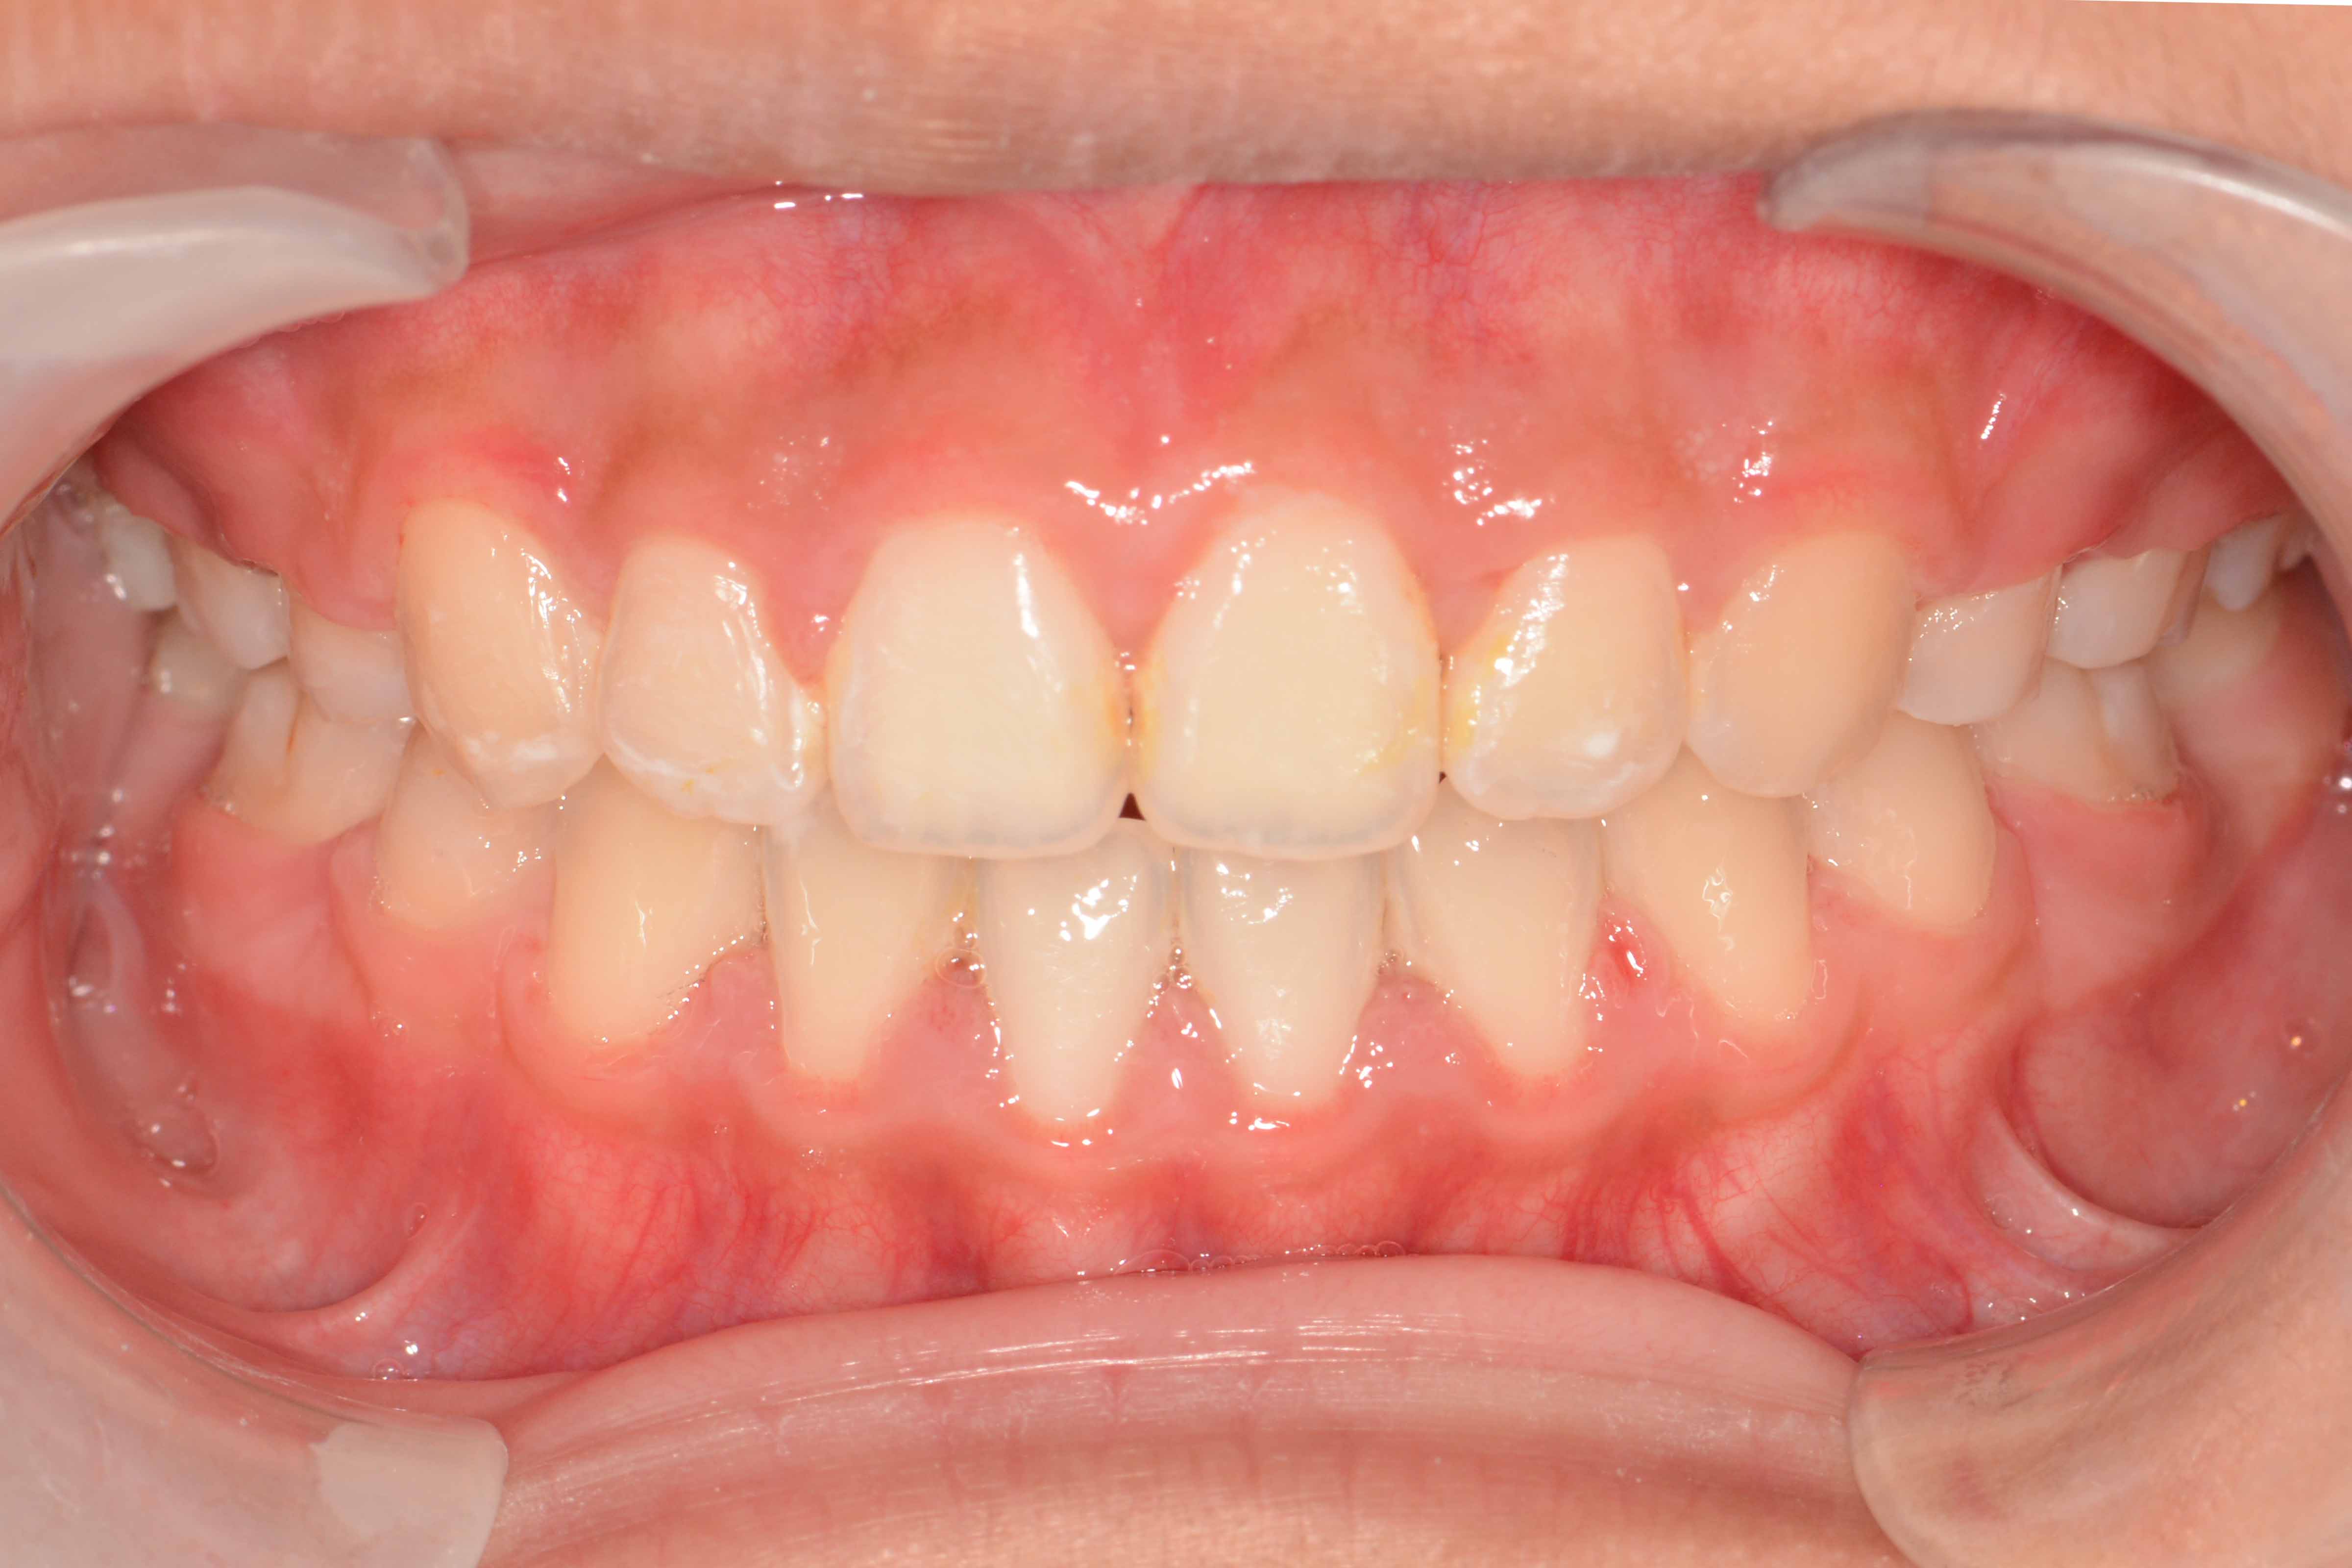

患者:14岁女性

主诉:前牙咬不住,进食不便

前牙区开颌3mm

诊断:安氏II类错颌畸形  开颌

矫治前: